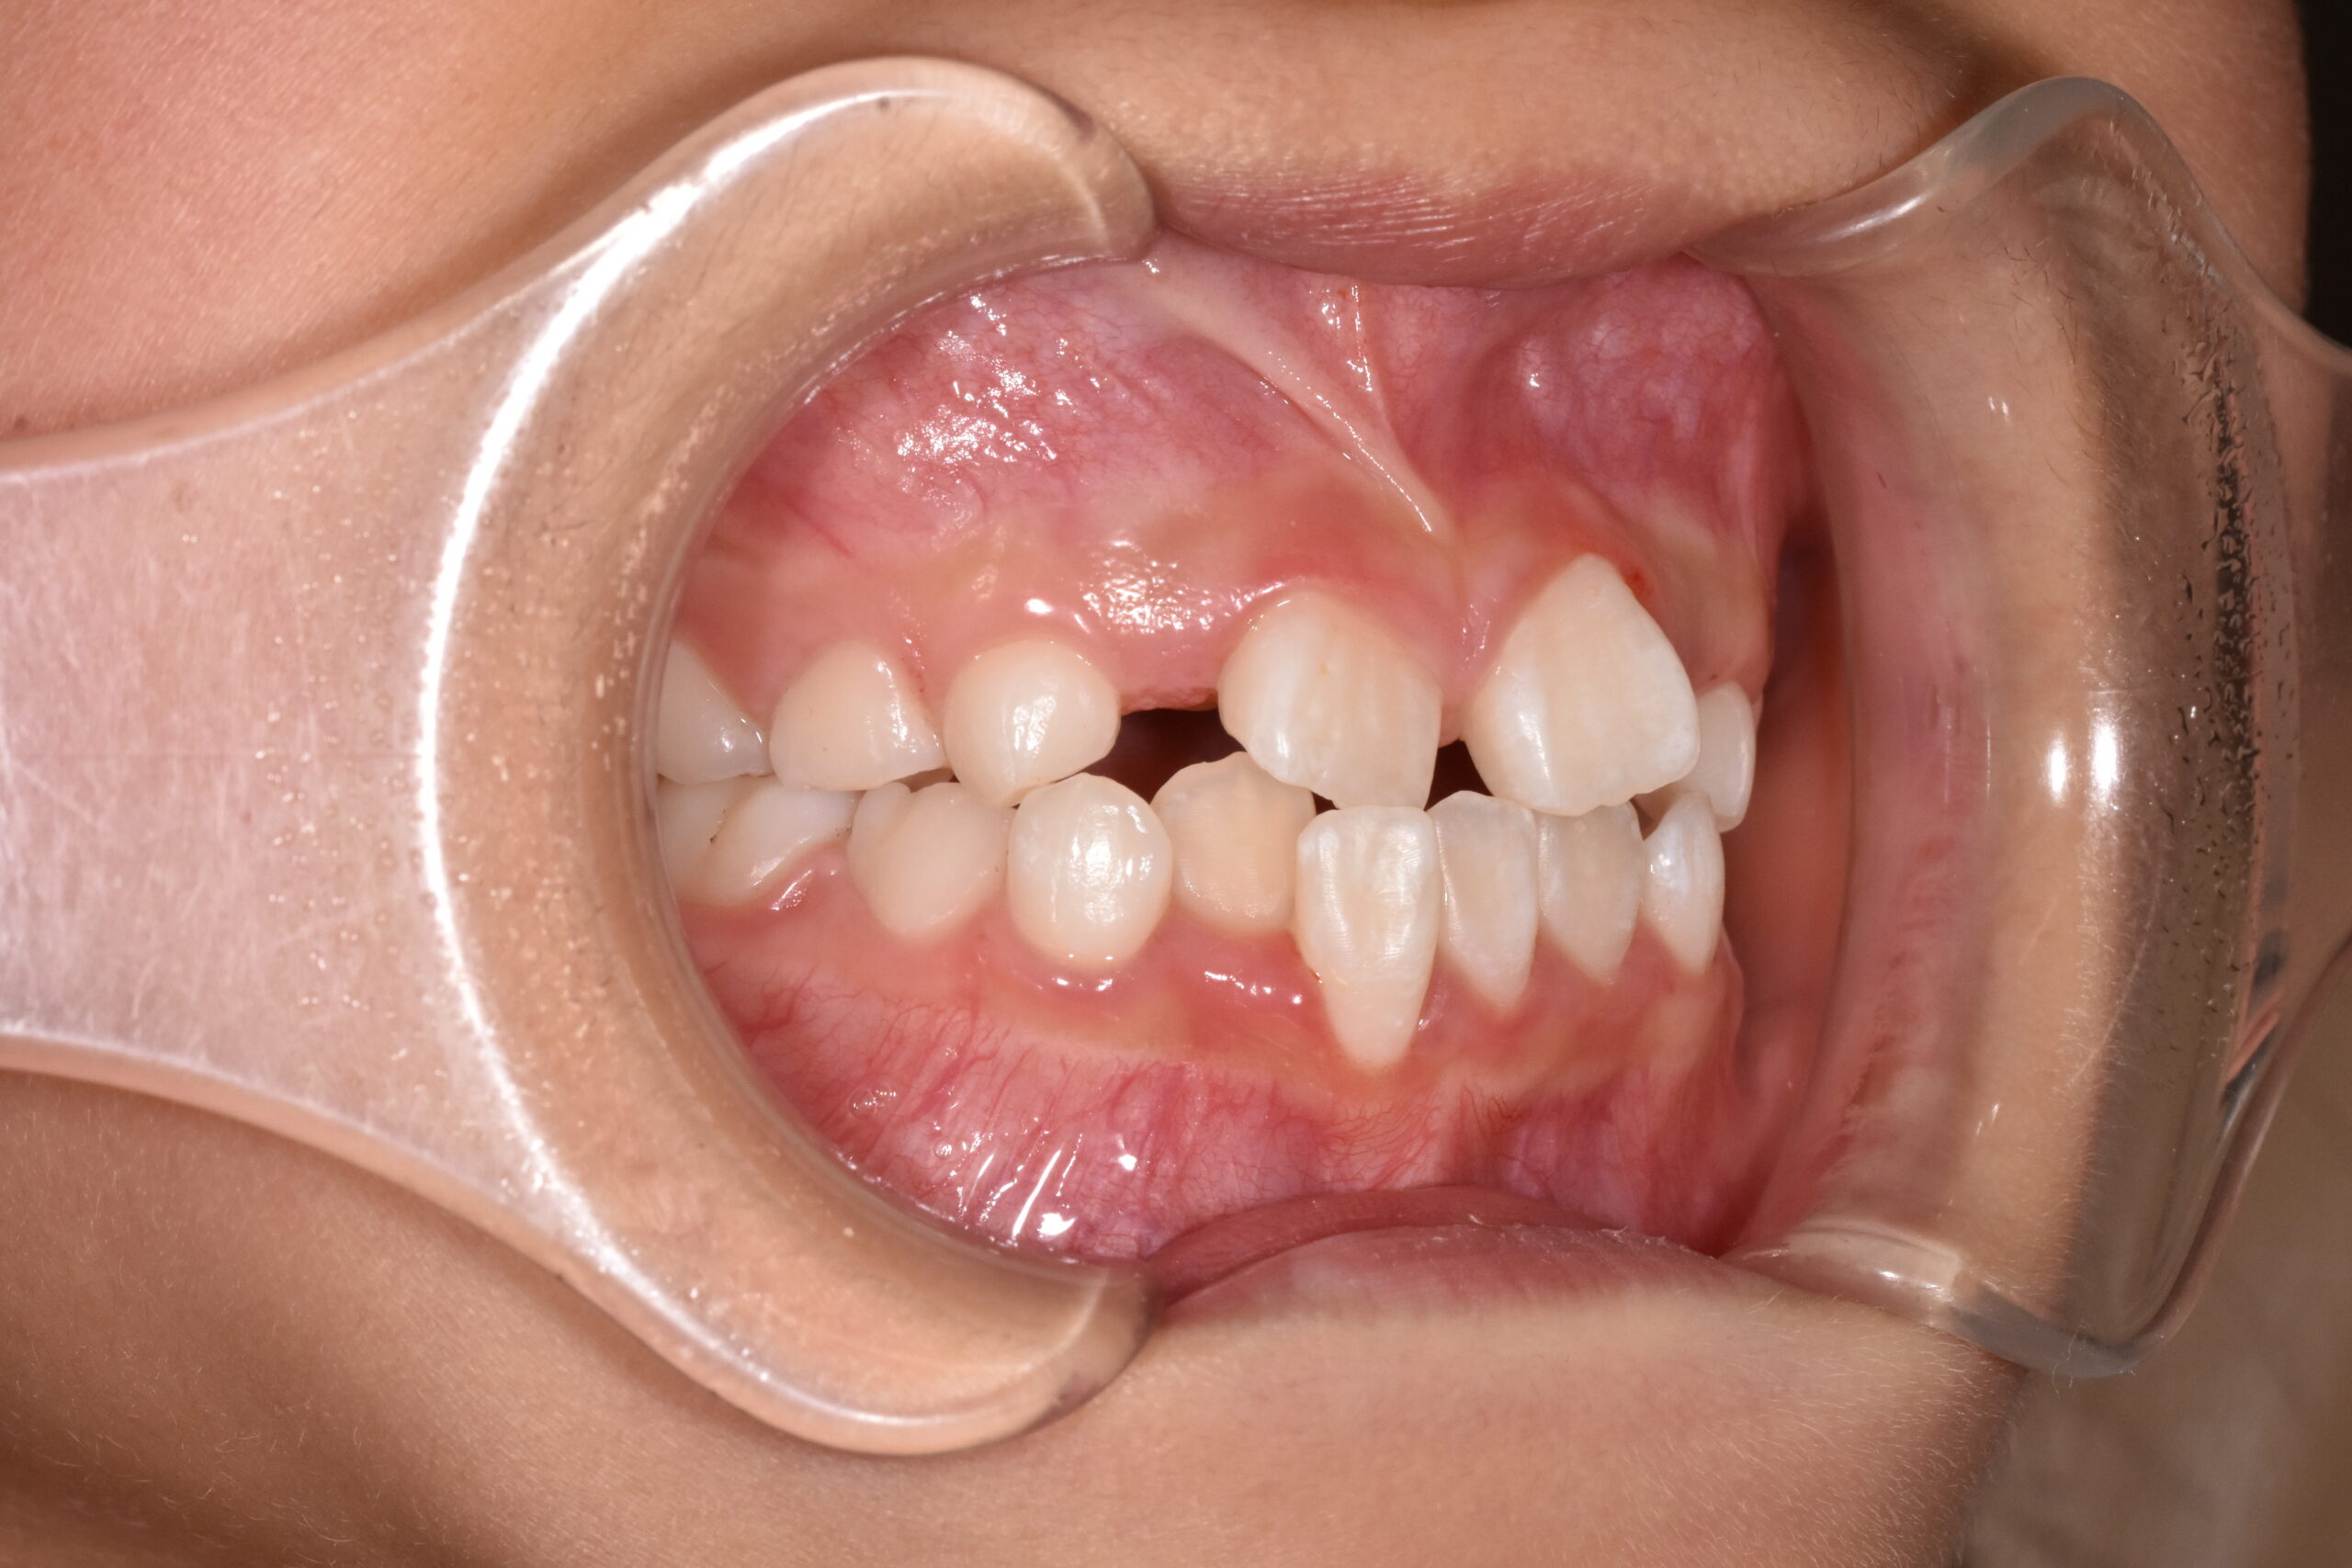

治療前

治療方法:

マウスピース型矯正

治療のポイント:

・成長を利用して改善

・機能(舌・呼吸)も同時にアプローチ